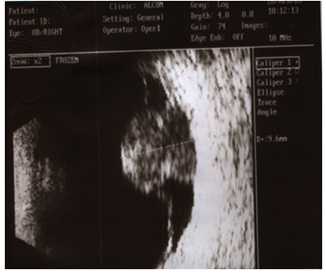

Представлен клинический случай 25-летней пациентки с остеомой хориоидеи, осложнённой хориоидальной неоваскуляризацией. Офтальмологическое обследование включало визометрию с определением максимально корригированной остроты зрения (МКОЗ); непрямую офтальмоскопию с помощью бесконтактной линзы MaxField 78D (Ocular Inc., США); оптическую когерентную томографию (ОКТ) выполняли на приборе Cirrus HD-OCT 5000 (Сarl Zeiss Meditec, Германия) и ОКТ-Ангио выполняли на приборе AngioVue (Оptovue, США), измерение площади неоваскулярного комплекса проводилось в программе Angio Analitic; аутофлюоресценцию в коротковолновом режиме (488 нм), мультиспектральное лазерное сканирование сетчатки (MultiColor), флюоресцеиновую ангиографию выполняли на приборе Spectralis HRA+OCT (Heidelberg Engineering Inc., Германия); исследование светочувствительности сетчатки выполняли на фундус-микропериметре MAIA TM (Center Vue, США). Ультразвуковое В-сканирование проводили на приборе Ultra Scan Imaging System (Alcon). Фоторегистрацию глазного дна проводили на фундус-камере Visucam 500 (Zeiss, Германия). Срок наблюдения составил 3 месяца.

OD: МКОЗ 0,9. Рефракция эмметропическая. Передний отрезок без патологических изменений, оптические среды прозрачные. Диск зрительного нерва бледно-розовый, контуры чёткие. Вокруг диска глубокий желтоватый очаг с чёткими фестончатыми границами и хорошо выраженной поверхностной сосудистой сетью. В зоне папилломакулярного пучка - единичные геморрагии. Над геморрагией фокус гиперпигментации. В макулярной зоне - без патологии. OS: МКОЗ 1,0. Рефракция эмметропическая. Передний и задний отрезок - без патологии. Аутофлюоресценция OD - зона опухоли соответствует гипоаутофлюоресцентному фокусу (зона дегенерации РПЭ). По краям фокуса определяется зона гипераутофлюоресценции, что указывает на увеличение метаболической активности в РПЭ вдоль края опухоли. В зоне активной ХНВ - фокус гипераутофлюоресценции. На флюоресцеиновых ангиограммах OD определяется ранняя пятнистая гиперфлюоресценция с последующим диффузным прокрашиванием в поздние фазы. В проекции ХНВ на ранней стадии определяется зона гиперфлюоресценции с чёткими границами, с усилением просачивания красителя на поздних стадиях. Аутофлюоресценция OS - соответствует норме. На ОКТ OD - в зоне папилломакулярного пучка определяется гиперрефлективный очаг на уровне пигментного эпителия, по краям которого определяются отслойки нейроэпителия. В самой структуре опухоли выявляются гиперрефлективные и гипорефлективные зоны, что соответствует ячеистой структуре кости. ОКТ OS - без патологии. По данным ОКТ-Ангио OD - площадь неоваскулярного комплекса 0,296 мм2. При исследовании светочувствительности макулярной зоны выявлено снижение средней светочувствительности центральной зоны сетчатки OD до 21,0 дБ. Для уточнения диагноза и проведения дифференциальной диагностики были проведены лабораторные тесты и антитела к инфекциям. Антитела были отрицательными. При проведении ультразвукового В-сканирования OD определяется гиперрефлективное образование, дающее орбитальную «тень» в виде «псевдо-ДЗН». Установлен диагноз - OD «остеома хориоидеи», осложнённая хориоидальной неоваскуляризацией правого глаза. С учётом клинической картины пациентке было назначено лечение: проведение интравитреальных инъекций Луцентиса № 3 по стандартной технологии с интервалом в 1 месяц в дозе 0,5 мг (0,05 мл) в условиях стерильной операционной. Критерием для продолжения лечения было сохранение активности ХНВ. При осмотре больной через 3 месяца выявлено повышение МКОЗ OD до 1,0; метаморфопсии не беспокоили. Вокруг диска - глубокий желтоватый очаг с чёткими фестончатыми границами сохраняется. В зоне папилломакулярного пучка - геморрагии не определяются. Интенсивность зоны гиперпигментации усилилась. В макулярной зоне - без изменений. ОКТ OD через 3 месяца - отмечается отсутствие отслоек нейроэпителия. В самой структуре опухоли сохраняются гиперрефлективные и гипорефлективные зоны. По данным ОКТ-Ангио, OD - площадь неоваскулярного комплекса снизилась до 0,166 мм2. Аутофлюоресценция OD - зона опухоли соответствует гипоаутофлюоресцентному фокусу. По краям фокуса определяется зона гипераутофлюоресценции. В зоне ХНВ - фокус гипераутофлюоресценции меньший по площади в сравнении с прежним исследованием. ФАГ OD - в проекции ХНВ на ранней стадии зона слабой гиперфлюоресценции меньшая по площади в сравнении с прежним исследованием. На поздних стадиях усиления просачивания красителя не определяется. В зоне опухоли сохраняется ранняя пятнистая гиперфлюоресценция с последующим диффузным прокрашиванием в поздние фазы. При исследовании светочувствительности макулярной зоны через 3 месяца наблюдения выявлено повышение средней светочувствительности центральной зоны сетчатки OD до 27,0 дБ.